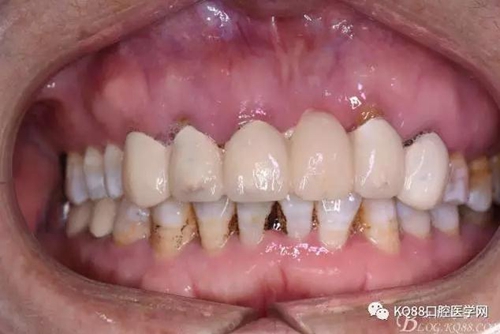

圖3.術(shù)前口內(nèi)正面照:12前庭溝輕度捫痛、有乒乓感